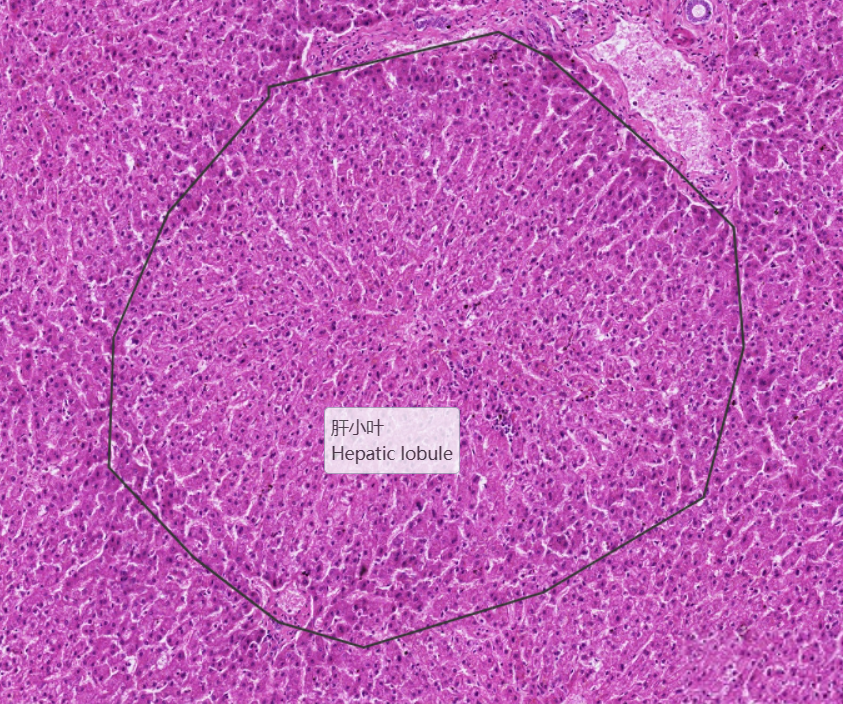

低倍镜观察:1. 肝小叶:呈多边形或不规则形,界限不清。中央静脉位于肝小叶内,但并非完全位于中央,且有的肝小叶中找不到中央静脉(与肝小叶的切面有关)。肝板及肝血窦均比较清楚。2. 门管区:在邻近几个肝小叶之间的结缔组织内,三种伴行的管道:(1)小叶间动脉:腔小壁厚,可见中膜环行平滑肌。(2)小叶间静脉:腔大壁薄,有时可见与血窦相连续。(3)小叶间胆管:管径较小,管壁衬以单层立方上皮,细胞呈立方形,胞浆清明,细胞核呈圆形,着色较深。

2.肝小叶